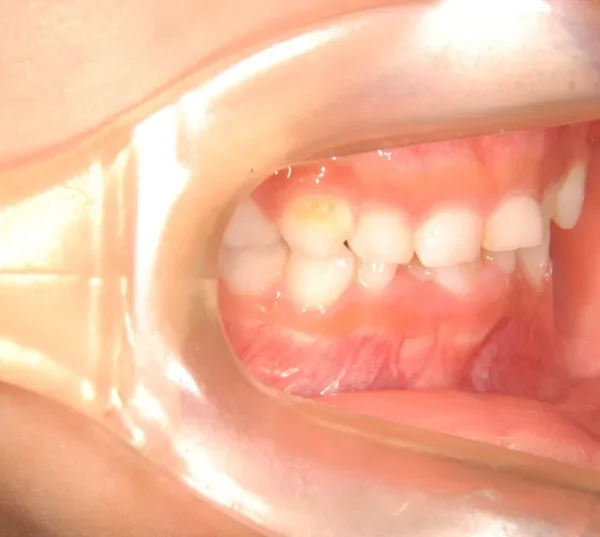

• 初診

初診時年齢 6歳まで (女性) 主訴 ガタガタ

診断名 叢生 装置名

下の歯がずれて生えています。

こどもの歯は下の2本しか抜けていませんが、放っておくとガタガタがきつくなるので、早い段階からの治療としました。